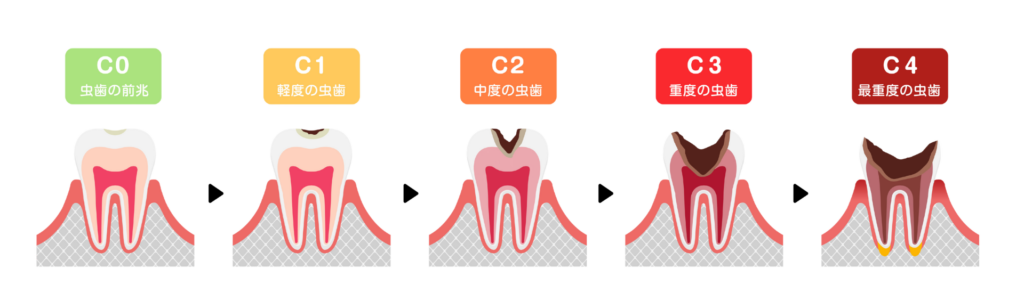

虫歯の進行段階と治療法

虫歯は自然治癒することがない疾患です。放置すればするほど進行し、治療期間も長く、費用もかさむことになります。

早期発見と早期治療が、歯を守るための最善策です。

C0:初期虫歯

歯の表面のエナメル質が溶け出し、白濁している状態です。まだ穴は空いていません。この段階であれば、歯を削る必要はありません。適切なブラッシング指導とフッ素塗布を行い、再石灰化を促すことで健康な状態に戻ることを目指します。

C1:エナメル質の虫歯

歯の表面に小さな穴が空いた状態です。痛みはほとんどありませんが、放置すると進行します。

虫歯部分を最小限削り、歯科用プラスチック(レジン)を詰めて修復します。1回の通院で治療が完了することがほとんどです。

C2:象牙質の虫歯

虫歯がエナメル質の内側にある象牙質まで進行した状態です。冷たいものや甘いものがしみたり、痛みを感じたりします。

範囲が小さい場合はレジンで修復しますが、範囲が広い場合は型取りを行い、詰め物(インレイ)を作製して装着します。

C3:神経まで達した虫歯

虫歯菌が歯の神経(歯髄)まで侵入し、激しい痛みや腫れを伴う状態です。

この段階になると、神経を取り除く「根管治療」が必要になります。

当院ではマイクロスコープ(歯科用顕微鏡)を使用し、肉眼では見えない根の先まで徹底的に汚染物質を除去します。その後、被せ物(クラウン)を装着して歯の機能を回復させます。

C4:歯根まで達した虫歯

歯の大部分が溶けてなくなり、根っこだけが残っている状態です。神経が死んでしまっているため痛みを感じないこともありますが、根の先に膿が溜まると再び激痛が生じます。

ここまで進行すると抜歯となるケースが多いですが、当院では可能な限り歯を残す方法を模索します。どうしても保存が不可能な場合に限り、抜歯を行い、インプラントや入れ歯、ブリッジなどで欠損を補います。